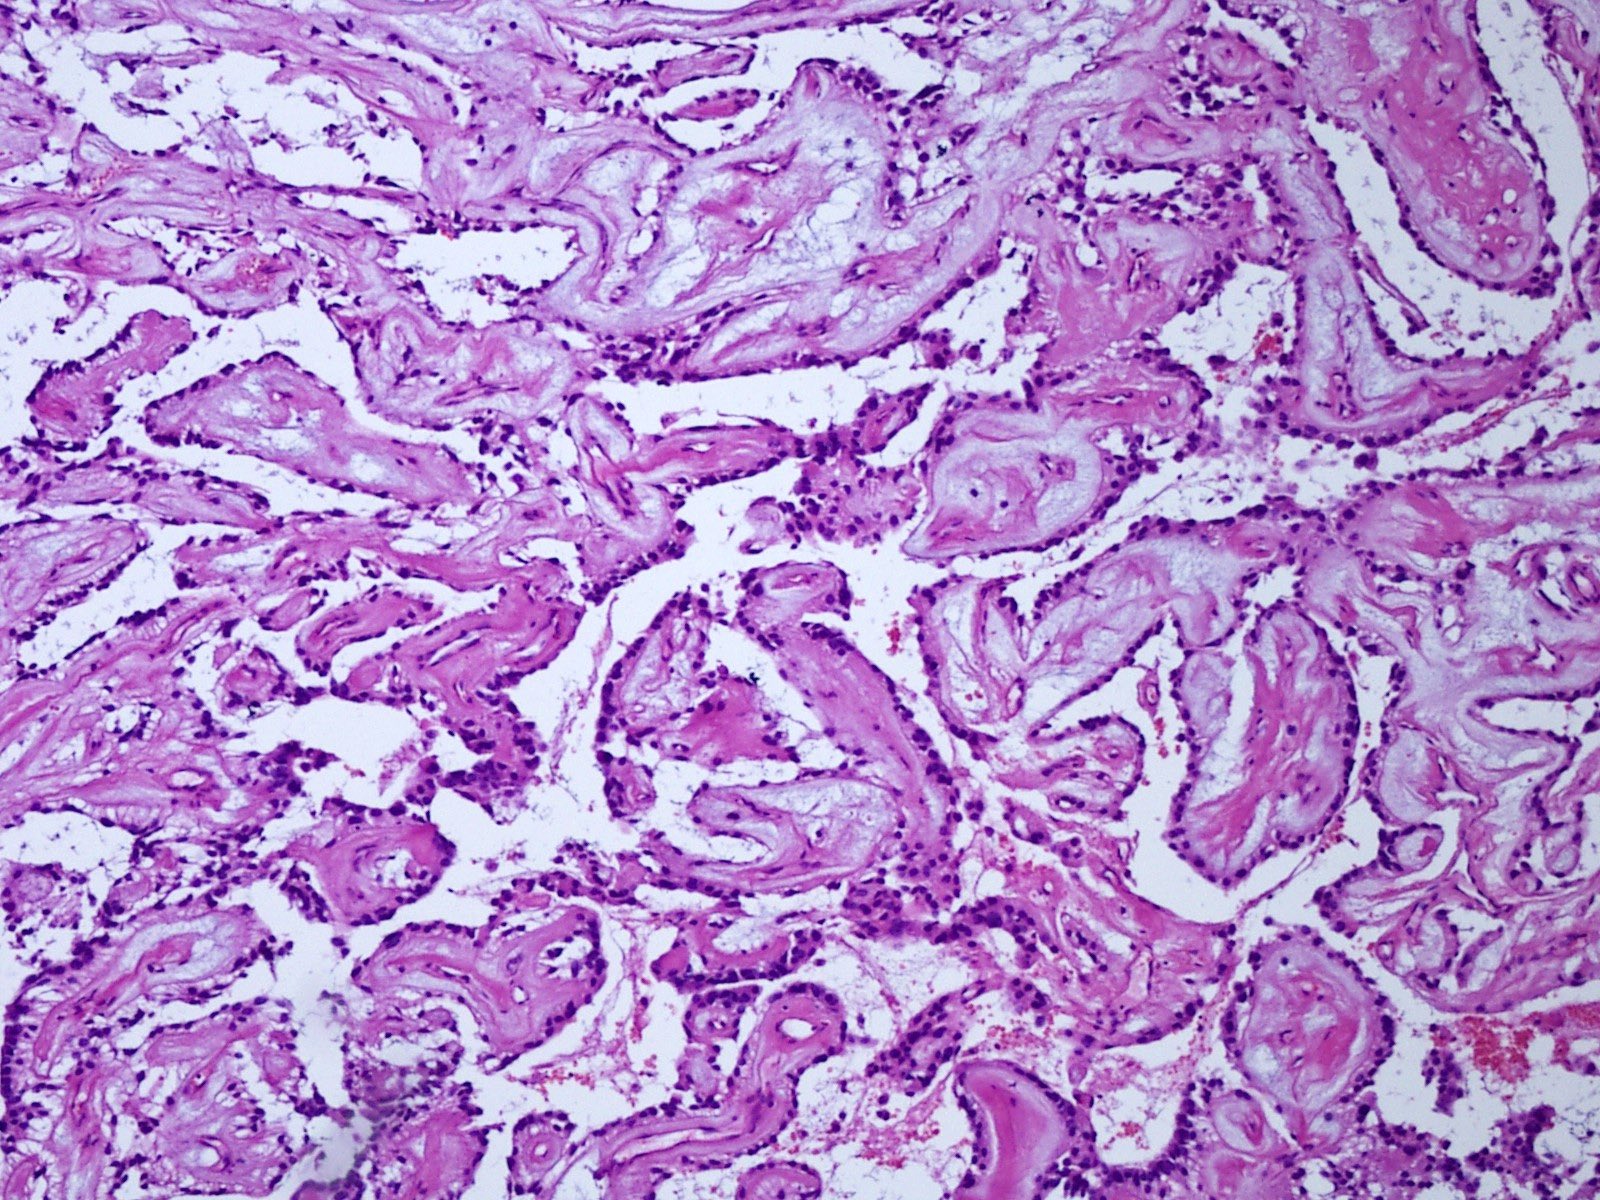

Microscopic (histologic) description

- Most common pattern is radial arrangement of cuboidal to epithelioid elongated glial tumor cells around hyalinized fibrovascular (central, often hyalinized blood vessels) cores in a papillary configuration

- Accumulation of basophilic myxoid material around blood vessels (myxoid stroma) and in microcysts

- Fascicular growth and spindle cells are common

Microscopic (histologic) images

- Schwannoma:

- Arises from nerve roots (myxopapillary ependymomas usually arise in the filum terminale)

- Usually, distinctive histological appearance from ependymoma; however, a paucicellular ependymoma with fascicular architecture may simulate schwannoma

- No Antoni A or B areas are present in ependymomas

- There are no nuclear or cytoplasmic inclusions in ependymomas

- Myxopapillary ependymomas have a delicate rather than densely collagenized capsule seen in schwannomas

- Schwannomas show pericellular reticulin and extensive immunostaining for laminin and type IV collagen